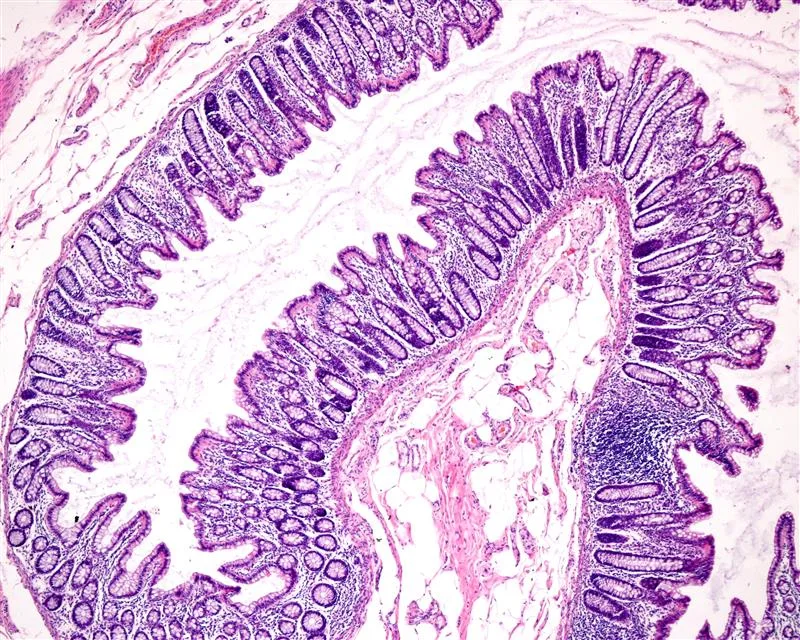

Histology reveals what symptoms, biomarkers, and endoscopy alone cannot. In GI trials, it provides direct evidence of inflammation, healing, structural changes, and treatment response — critical for demonstrating biological effect across indications such as IBD, EoE, celiac disease, and microscopic colitis.

- Inflammatory infiltrates and immune activity

- Epithelial injury, mucosal integrity, and repair

- Fibrosis, extracellular matrix remodeling, and architectural distortion